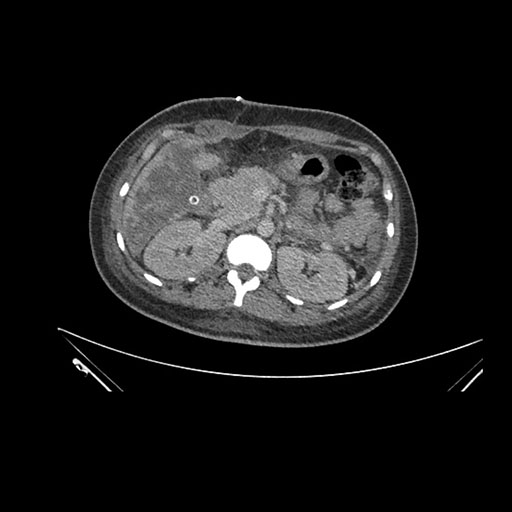

Imaging Analysis

Look through the patient's CT scan to identify any areas of concern for the necessary procedure.

Axial Arterial

Based on initial findings, which issue(s) would you be most concerned about?